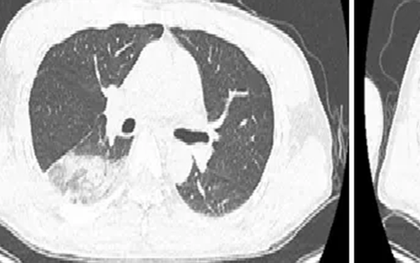

Người đàn ông bệnh nặng vì thích chơi chim

Nam bệnh nhân 46 tuổi đã sốt cao liên tục suốt 10 ngày, gan thận tổn thương nặng.